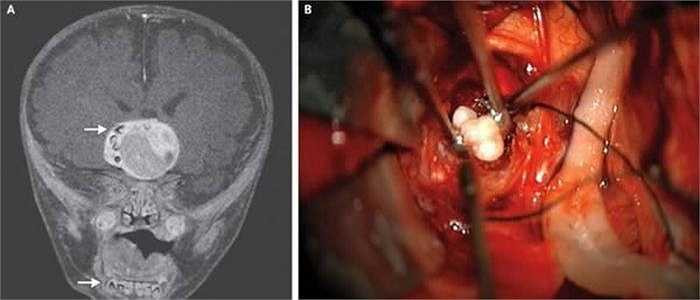

Một bé sơ sinh 4 tháng tuổi sống tại bang Maryland, Mỹ là trường hợp đầu tiên mọc răng trong não. Được biết, tình trạng não răng mọc trong não bị gây ra bởi một khối u não dạng hiếm.